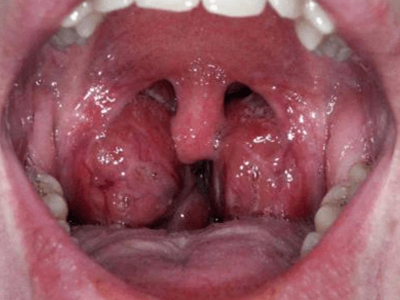

急性滤泡性扁桃体炎症状图片

急性滤泡性扁桃体炎发作时,扁桃体充血、肿胀,甚至出现化脓性炎症,在隐窝口之间的黏膜下,可出现黄白色斑点。患者可有咽痛、吞咽困难等临床症状。